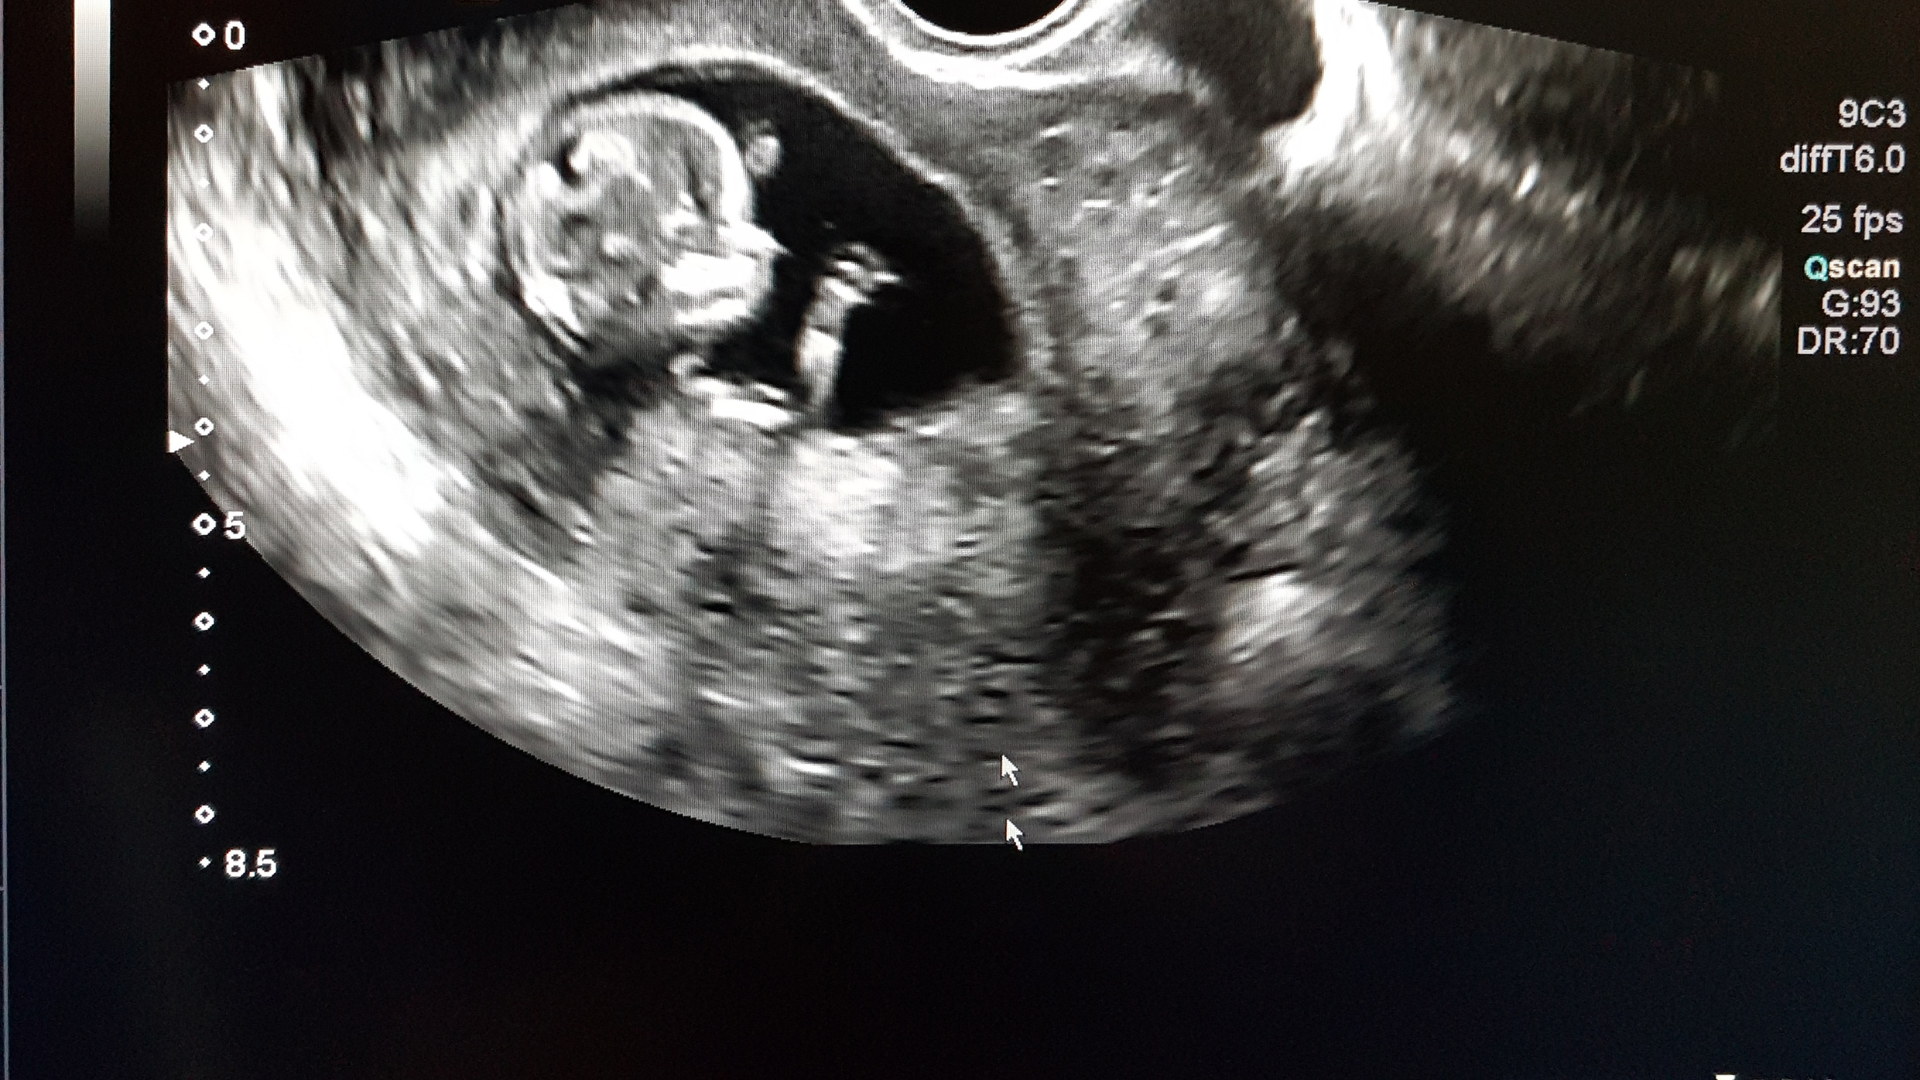

Thai chậm phát triển ở những tuần đầu được mô tả khi kích thước hoặc cân nặng thai nhi thấp hơn so với mức chuẩn tính theo tuổi thai và bé chưa đạt được tiềm năng tăng trưởng bình thường của cơ thể. Tình trạng này thường được phát hiện thông qua siêu âm khi bác sĩ đánh giá các chỉ số như chiều dài đầu mông, vòng bụng và cân nặng ước tính.

Khi siêu âm, bác sĩ sẽ dựa vào các chỉ số để theo dõi thai như: Kích thước chiều dài đầu mông, vòng bụng và cân nặng ước tính. Nếu các chỉ số này thấp hơn rõ rệt so với biểu đồ chuẩn thì có thể xem xét đến tình trạng thai chậm phát triển ở những tuần đầu. Ngoài ra, bác sĩ còn có thể đánh giá sự hoạt động của nhau thai qua dòng chảy mạch máu. Nếu có bất thường về dòng chảy thì nguy cơ suy giảm dinh dưỡng đến thai nhi có thể tăng lên.